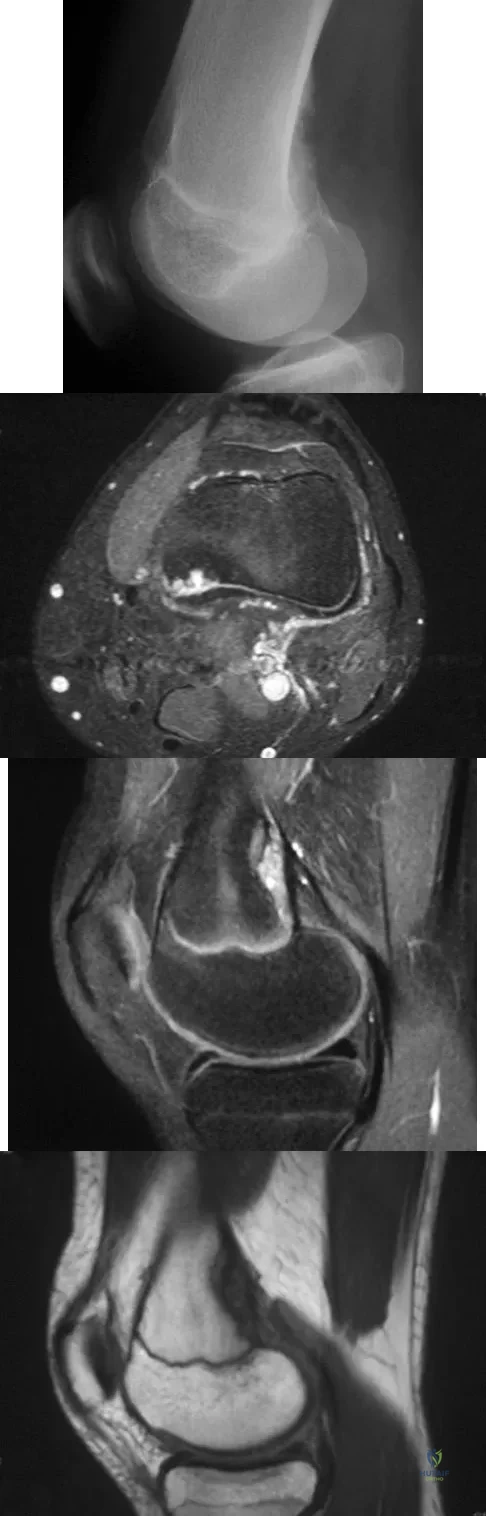

Question 76

A 14-year-old girl reports bilateral patellofemoral symptoms. Based on the radiograph and MRI scans shown in Figures 23a through 23d, what is the next most appropriate step in management of the lesion?

Explanation